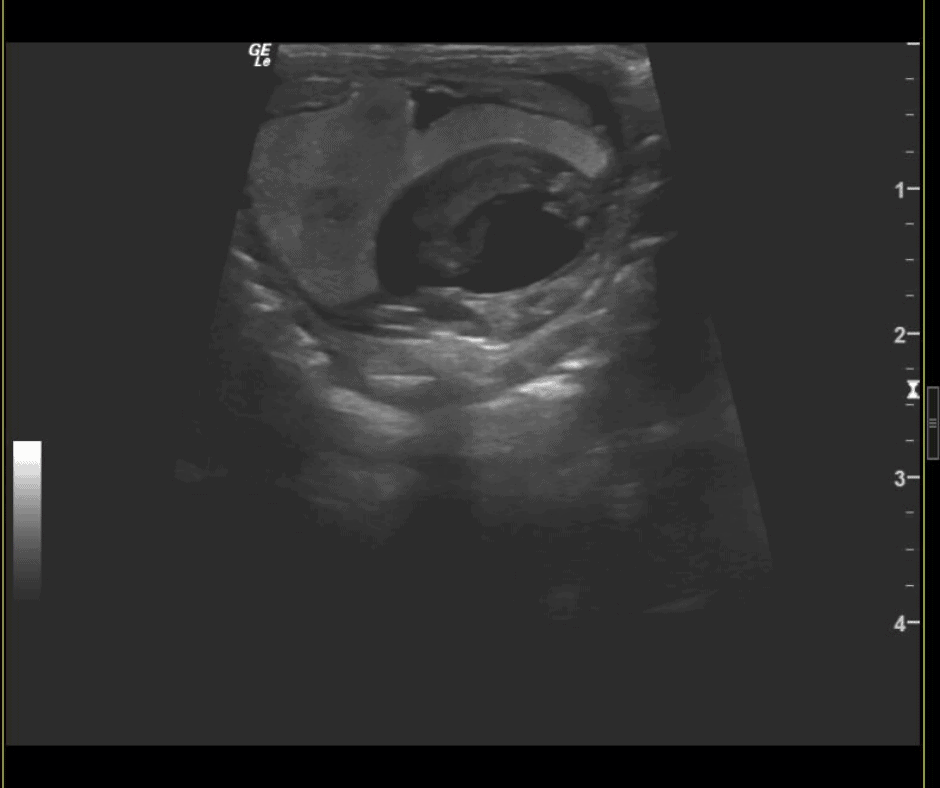

On July 4th we welcomed three tiger rattlesnakes. The gravid (pregnant) female tiger rattlesnake was taken to the Joyce Corrigan Animal Care Center twice for ultrasound exams. The ultra sound images from March 5 show the developing eggs, while the images from March 14 show the snake fetus.